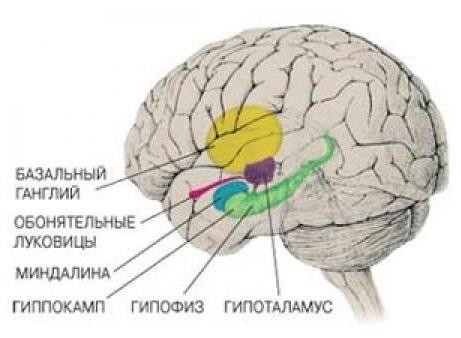

Физиология памяти: Механизмы и исследования